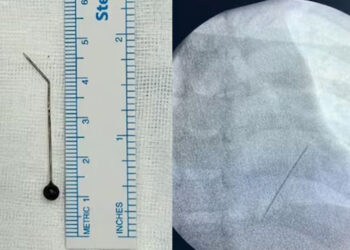

കടുത്ത ചുമയും രക്തസ്രാവവും; ഏഴു വയസുകാരന്റെ ശ്വാസകോശത്തിൽ നിന്നും കണ്ടെത്തിയത് 5 സെന്റിമീറ്റർ നീളമുള്ള ഹിജാബ് പിൻ

കൊച്ചി: കടുത്ത ചുമയും രക്തസ്രാവവും മൂലം അവശനിലയിലായ ഏഴുവയസുകാരന്റെ ശ്വാസകോശത്തിൽ നിന്നും പുറത്തെടുത്തത് ഹിജാബ് പിൻ. മാലിദ്വീപ് സ്വദേശിയായ കുട്ടിയുടെ ശ്വാസകോശത്തിൽ അപകടകരമായ വിധം കിടന്നിരുന്ന പിൻ ...